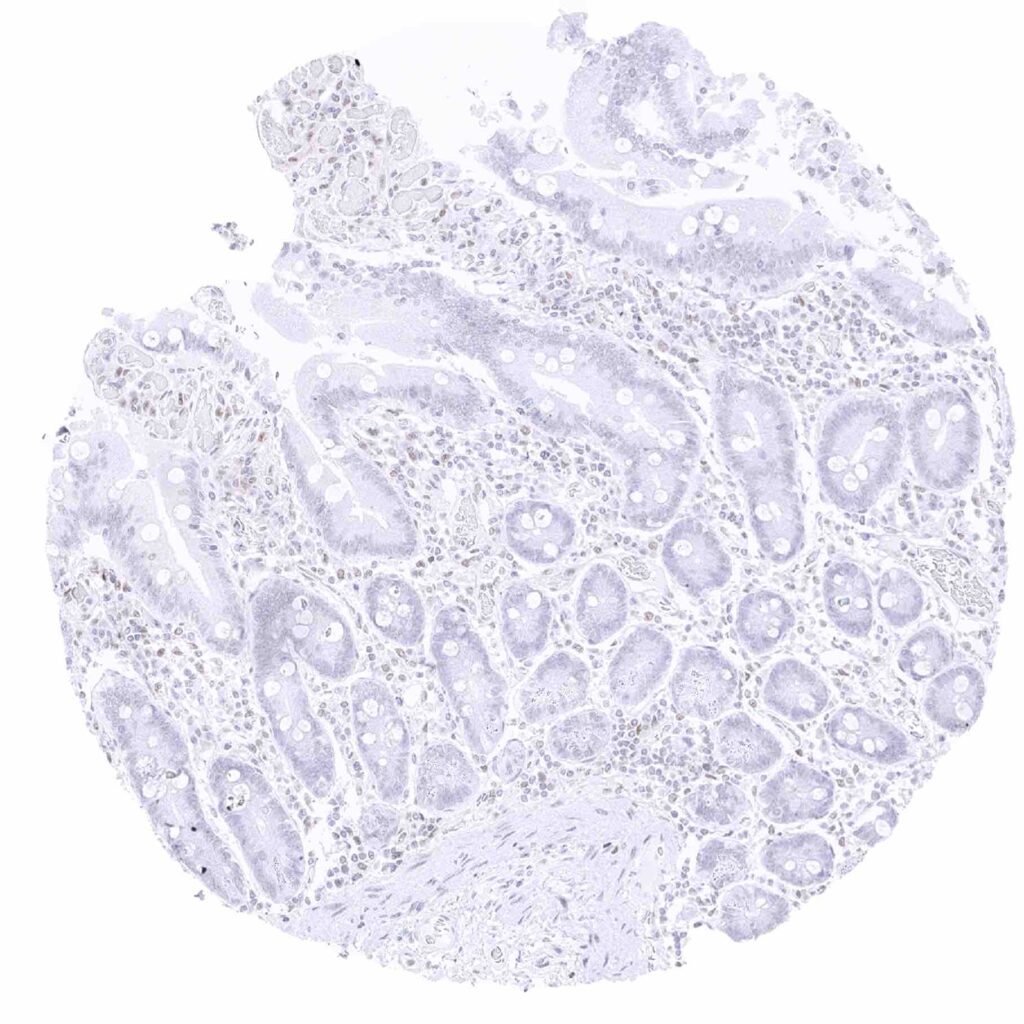

Colon descendens, mucosa – Some surface epithelial exhibit a faint TFE3 staining while inflammatory cells (macrophages_) show a moderate positivity